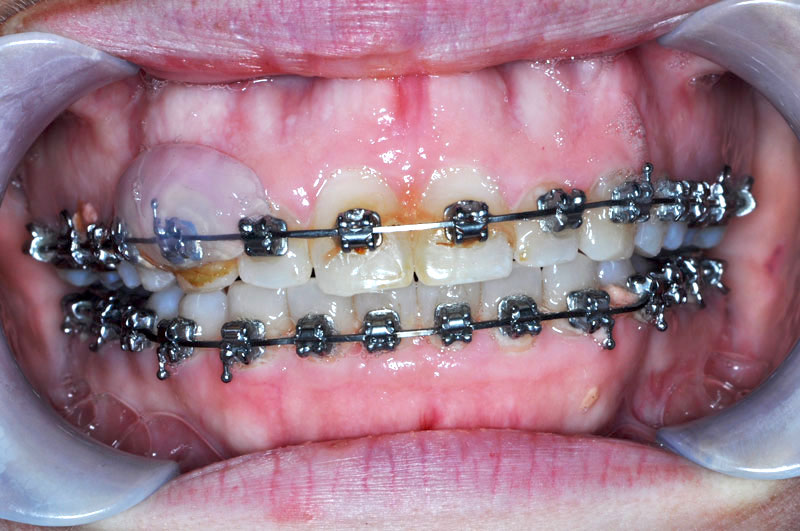

Case 18

Problems

- Vertical maxillary hyperplasia

- Nasal airway obstruction secondary to inferior turbinate hypertrophy

- Mandibular retrognathia

- Excess vertical chin height

Surgical Procedures Performed

- Bilateral sagittal split ramus osteotomies to advance the mandible

- Maxillary Le Fort I osteotomy to vertically impact the maxilla

- Bilateral inferior turbinectomies to improve the nasal airway

- Vertical reduction and advancement of the chin